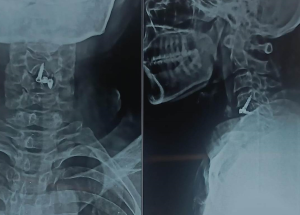

Expert spine services including minimally invasive surgery, pain management, and deformity correction.